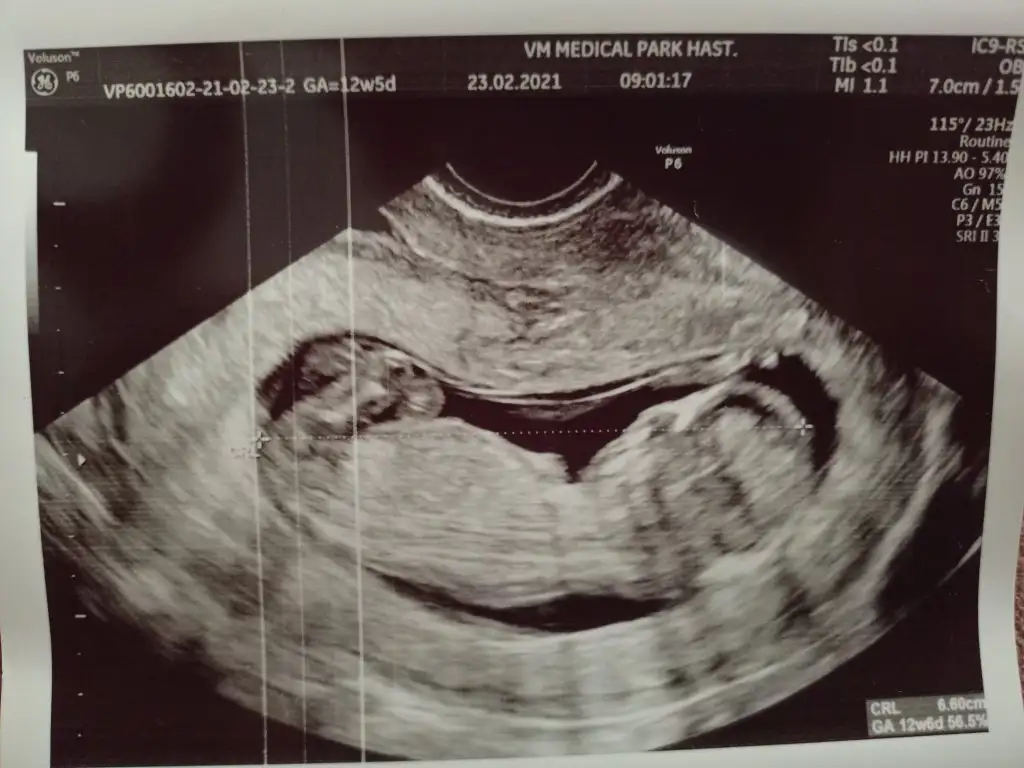

Kızlar Merhaba, bugün 12+5 ve ikili tarama için ultrason yapıldı. CRL 6.6 haftası ile uyumluymuş ancak ense kalınlığı 2.3 çıktı. Doktorum sınırın 2.5 olduğunu ve sınıra yakın olduğu için Down Sendromu riski içerdiğini söyledi. Nipt önerdi ancak bunun için kan tahlilinin de sonucunu bekliyorum. 26 yaşıma yeni girdim, hep sağlıklı beslenirim, alkol ve sigara kullanmıyorum. Yani risk grubunda değilim bu yüzden telaşlıda değilim ama yine de moralim bozuldu. Benzeri bir durum ile karşılaşan oldu mu?

Evet göründü, ölçümünü yaptı 0.31 cm ancak hiç onun hakkında bir şey söylemedi. Çok teşekkür ederim ilginiz için🙏 IMG20210223143857.webp